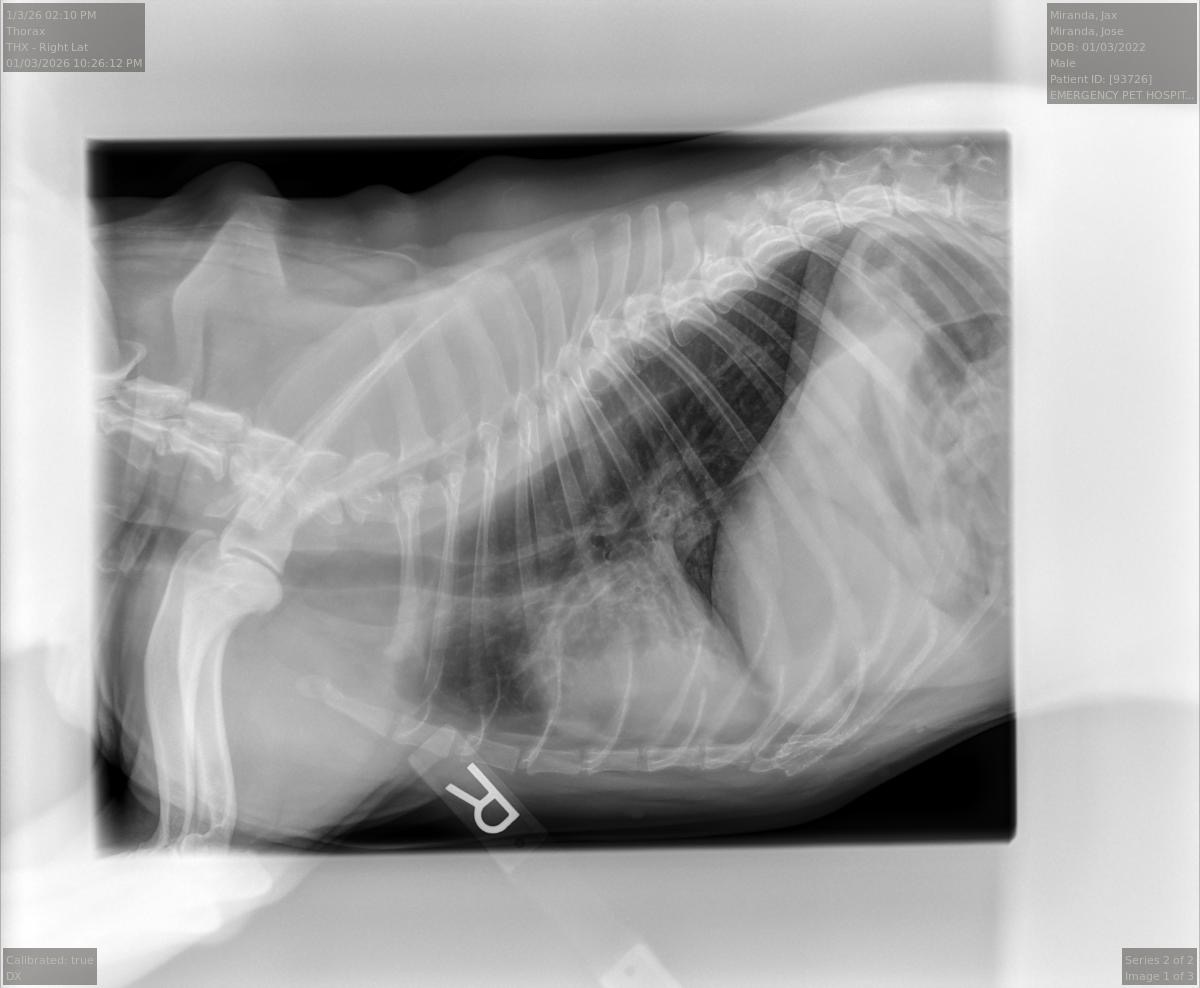

This is Jax. He is currently at the Loma Linda Animal Hospital due to unexpected illnesses that he got in December. We are so distraught to see our healthy and active doggy so weak and ill. As you can see in the picture above he was always smiling and super active and playful. When we initially took him for his examination he was diagnosed with pancreatitis, gastrointestinal issues, and aspiration pneumonia at Veterinary Emergency Center of Redlands. He has been ill for about a month now and has not yet recovered. We have been tirelessly trying to get him well but not having sufficient money to get the medical care that he needs has been so heartbreaking. I would be so grateful to receive any amount of donation to pay for his current and future medical expenses. If you’re only able to share that would be great or even just a prayer, I would greatly appreciate it. Jax needs to stay at the hospital so he can remain hydrated as he has an extremely difficult time drinking water and has not ate for about 3 weeks. The mega esophagus issue as well as the pancreatitis do not allow for him to keep water or food in his stomach and is throwing up constantly. The doctor said that the esophagus does not close when he does try to drink therefore causing the liquids to not digest and throws up. He needs to be connected to IV fluids that keep him hydrated with nutrients, antibiotics and medicine to address his stomach/ digestive issues. He is so close to recovery but will have difficulty overcoming his illnesses if he does not remain hydrated until he is well from the mega esophagus issue. Once that is cured he can begin to start eating. We have so much hope in the veterinarians and faith that Jax will overcome this and be the great ball of energy that he was. We miss the love, warmth and immeasurable energy that he brings into our lives. Thank you so much for your support and thank you for any amount of donations.